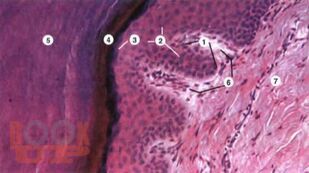

В монографии представлены результаты оригинальных исследований, посвященных судебно-медицинской оценке резаных и рубленых повреждений "барьерных" тканей волосистой части головы, с целью установления их морфологических особенностей в зависимости от действия режущих и рубящих объектов, имеющих лезвия различной остроты. Авторами на основании экспериментальных исследований, подтвержденных практическими наблюдениями установлено, что объективная экспертная оценка морфологических особенностей повреждений "барьерных" тканей волосистой части головы от различной остроты лезвия возможно только с учетом их анатомо-морфологических свойств. Разработан алгоритм экспертной оценки повреждений "барьерных" тканей волосистой части головы, позволяющий объективно установить механизм их образования и выраженность остроты лезвия.

Монография предназначена для практических судебно-медицинских экспертов, травматологов, хирургов, а также для преподавателей и студентов медицинских вузов.